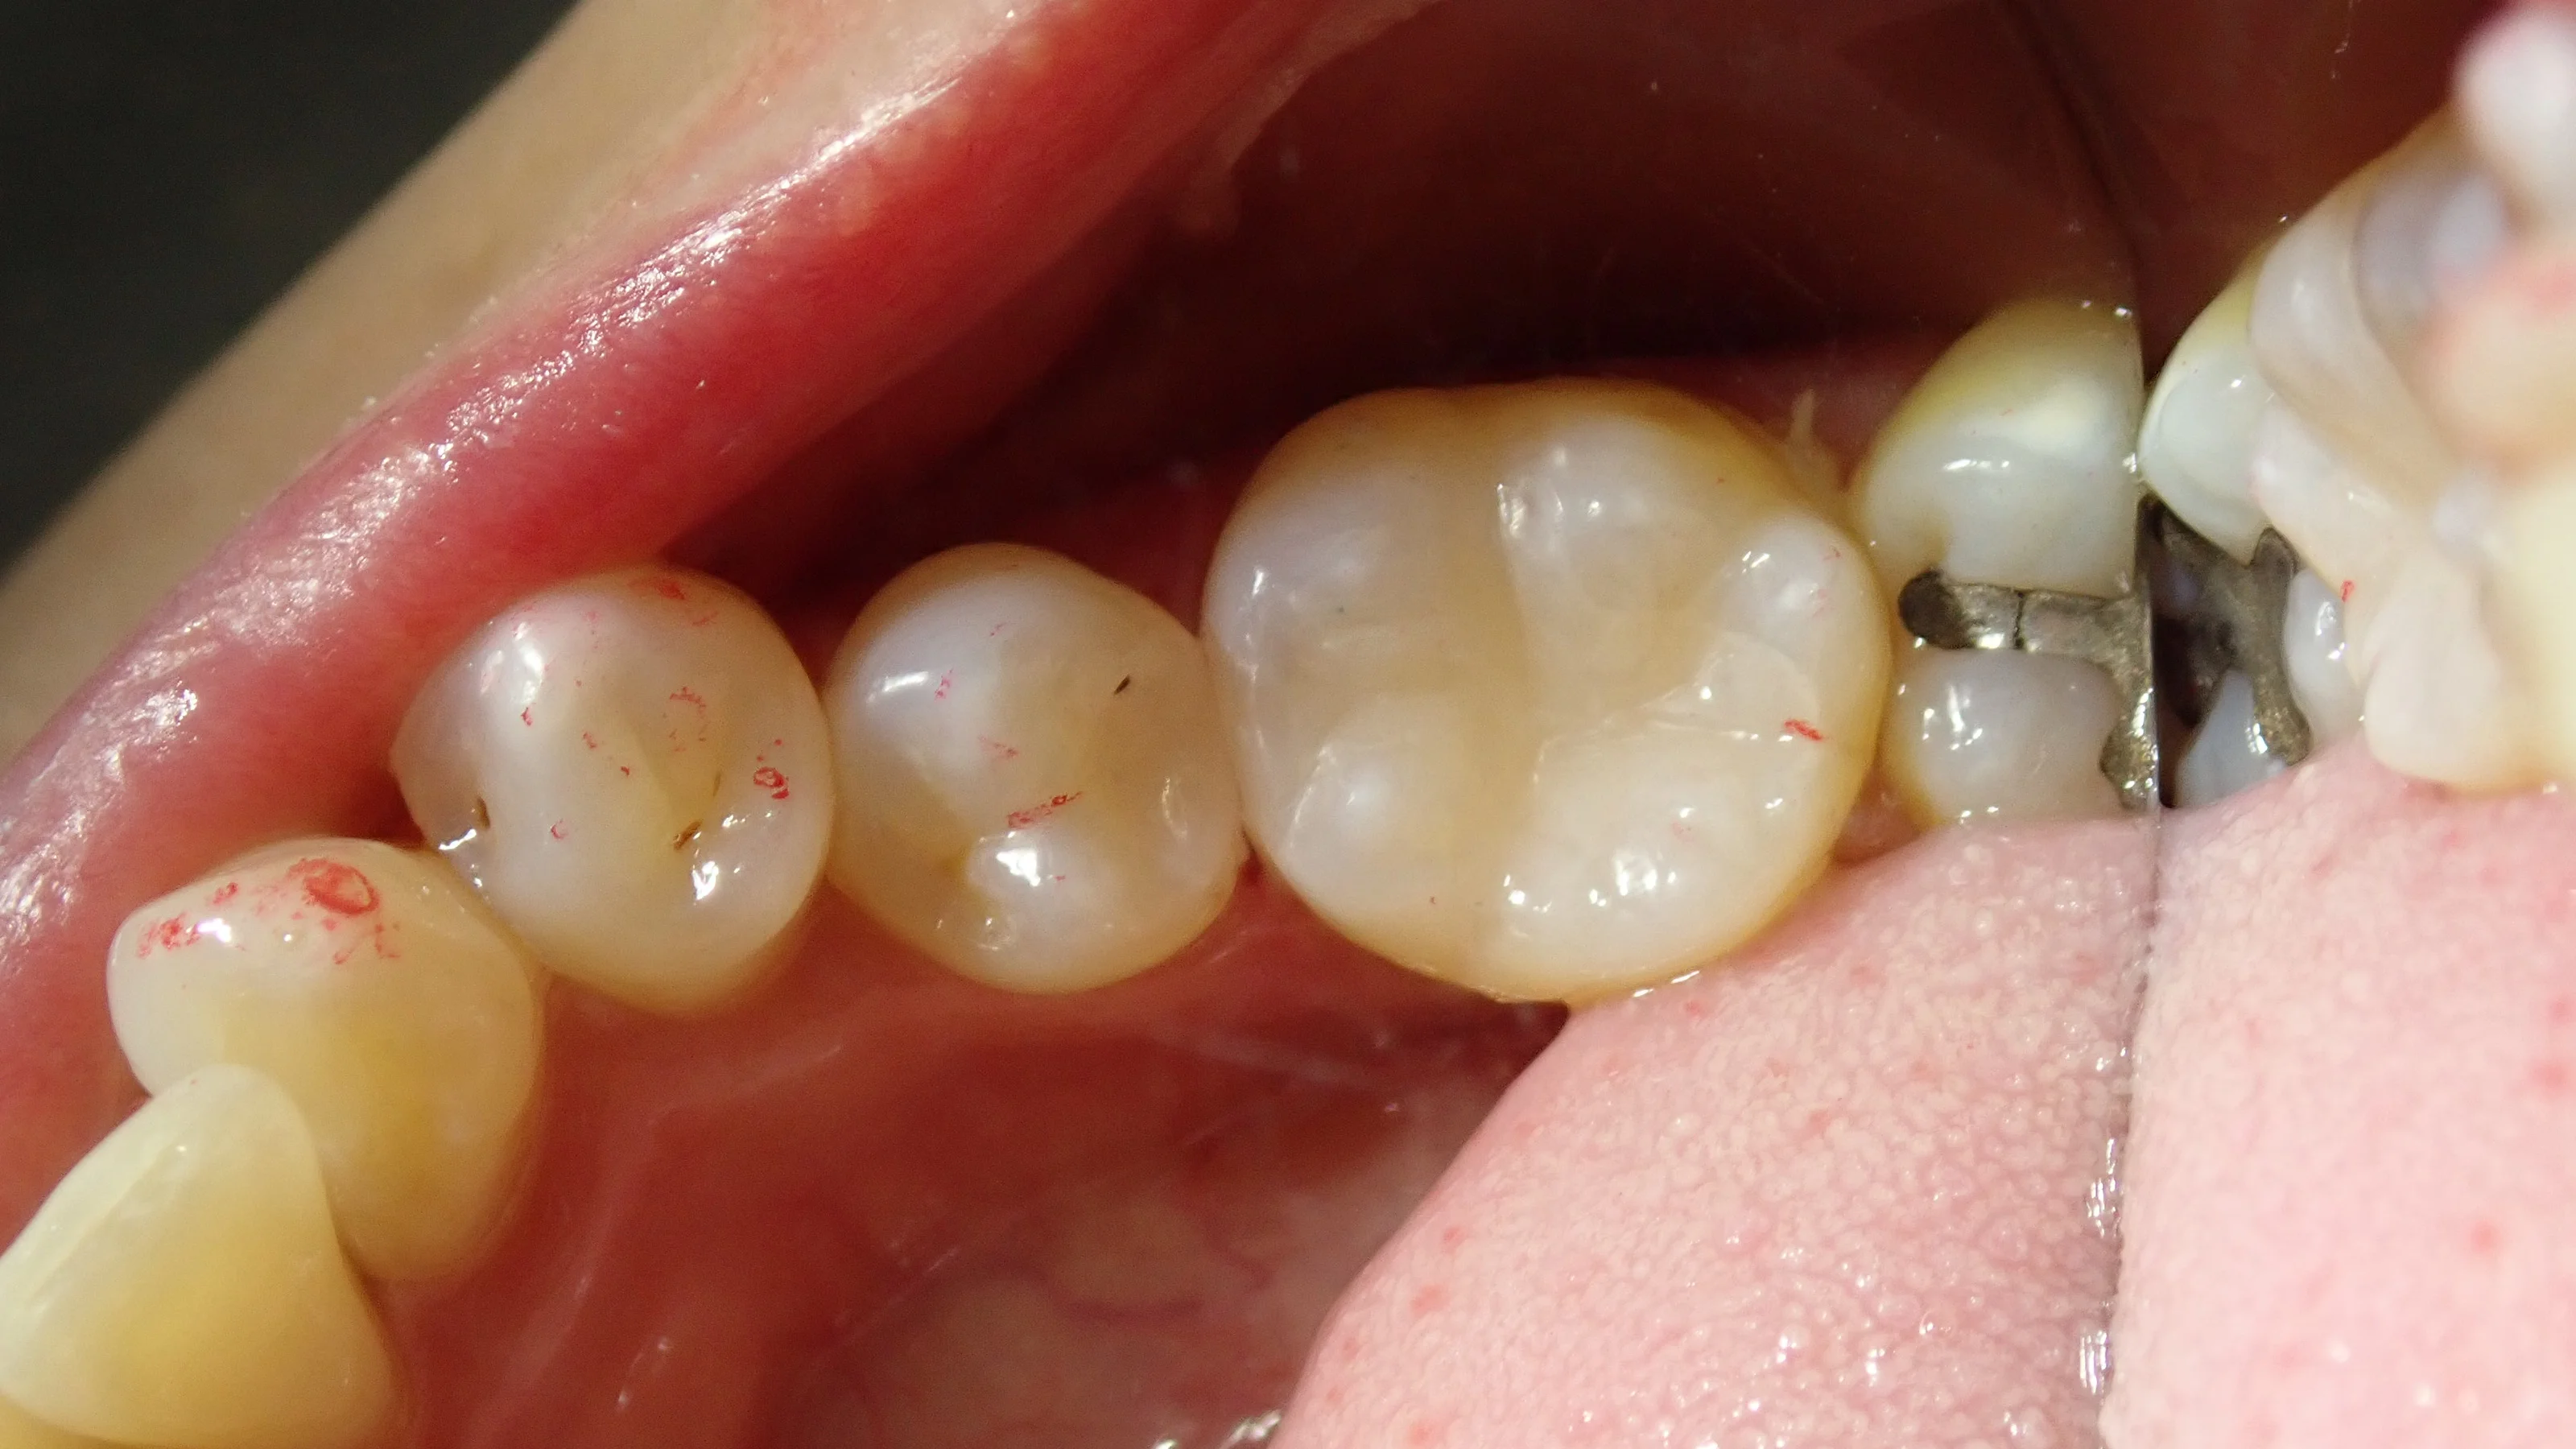

そしてこれが、詰め終わった状態です。

ある程度色もしっかりと合っているかと思います。

コンポジットレジンはこの歯の溝を再現するかどうかも結構意見が分かれてきますが、私は、食べ物を綺麗に排出するためにも必要な構造だと思ってますので、なるべく再現するようにはしています。

平なコンポジットレジン=粗悪ってことはないので、その点は安心してくださいね。